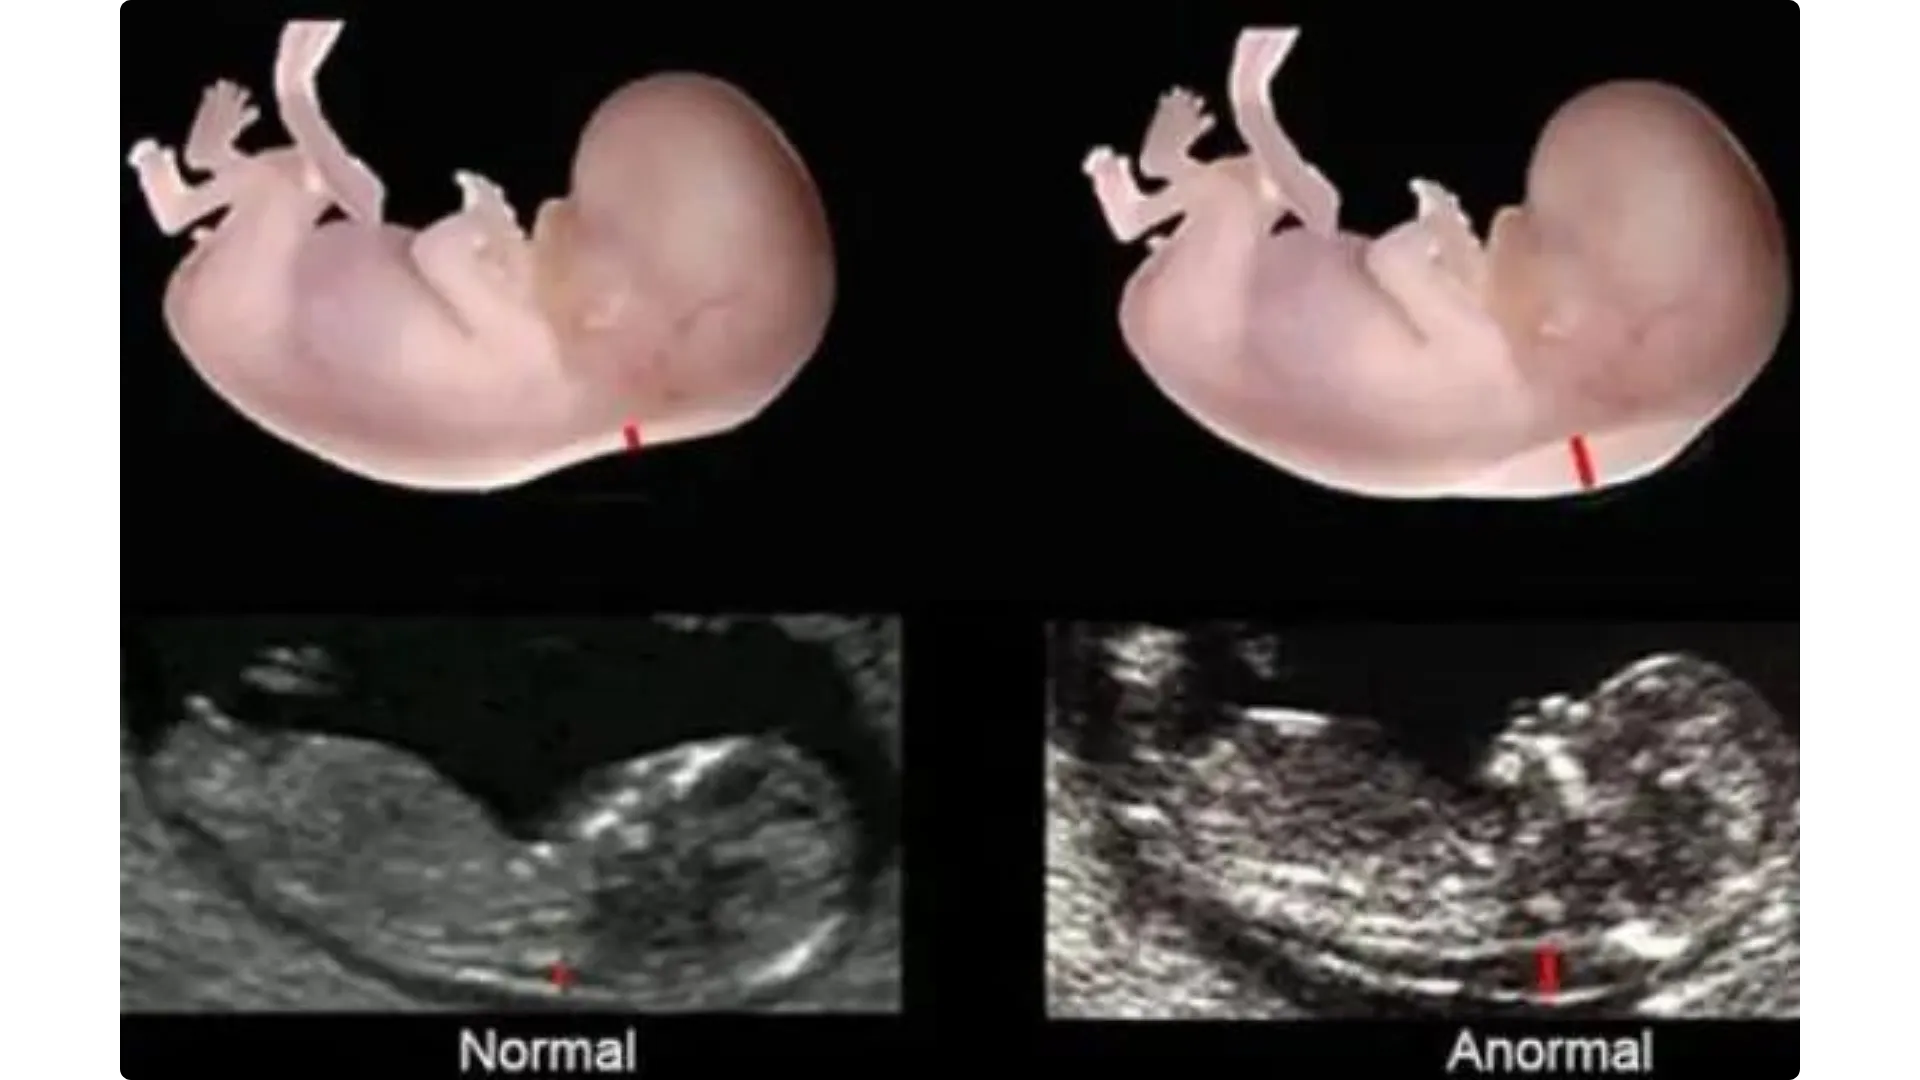

Ecografia del 2° Trimestre

L’indagine ecografica per la diagnosi di anomalie fetali deve essere offerta di routine tra 19+0 e 21+0.

L’indagine ecografica per la diagnosi di anomalie fetali consente di:

- compiere una scelta riproduttiva consapevole e decidere per tempo per un’interruzione di gravidanza;

- preparare i futuri genitori alla gestione di disabilità, eventuali trattamenti, cure palliative;

- programmare la nascita in centri specializzati;

- considerare eventuali interventi intrauterini.

L’ecografia del 2° trimestre viene chiamata morfologica proprio perchè mirata principalmente ad analizzare la morfologia del feto, per:

- controllare la vitalità del feto;

- osservare l’anatomia del feto;

- controllare lo sviluppo del feto.

Inoltre valuta la quantità di liquido amniotico, la localizzazione placentare e il sesso del nascituro.